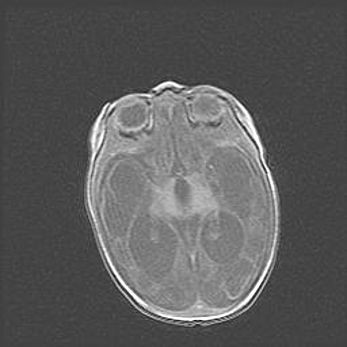

Наружная гидроцефалия с возможной атрофией височных областей.

Возраст: 28 дней

Вес: 3670 г

Пол: мужской

Окружность головы: 38 см

Срок гестации: 40 недель

Гидроцефалия головного мозга у новорожденных – это заболевание, которое характеризуется скоплением избыточного количества спинномозговой жидкости в желудочковой системе головного мозга в результате затруднения её перемещения от места выработки к месту поглощения в кровеносную систему или вследствие нарушения абсорбции. При открытой наружной форме гидроцефалии у новорожденных расширяются и переполняются субарахноидные пространства.

При нормотензивных  формах,  которые,  как  правило,  являются  следствием  перенесенных ишемических  повреждений  паренхимы  мозга,  возможно  сочетание микроцефалии  с нормотензивной гидроцефалией. В основе данных изменений лежит атрофия больших полушарий с преимущественной  локализацией  в  лобно-височных  областях.